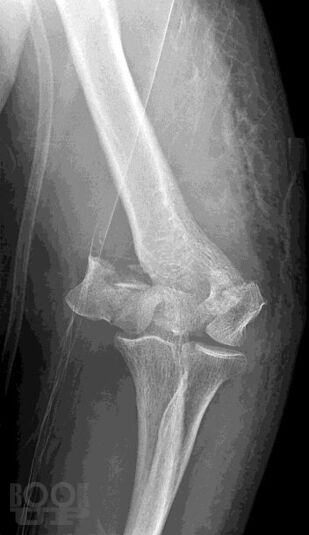

Учебно-практическое издание содержит ситуационные задания по наиболее распространенным и сложным разделам патологии опорно-двигательной системы (повреждения и заболевания верхних и нижних конечностей, позвоночника, повреждения и заболевания детского возраста и остеоонкология). Материал ситуационных заданий основывается на практическом опыте мирового сообщества травматологов-ортопедов. Для удобства восприятия материала эталоны ответов на ситуационные задания расположены в конце каждого задания. Практикум предназначен для ординаторов, аспирантов и врачей травматологов-ортопедов, обучающихся по специальности «Травматология и ортопедия».